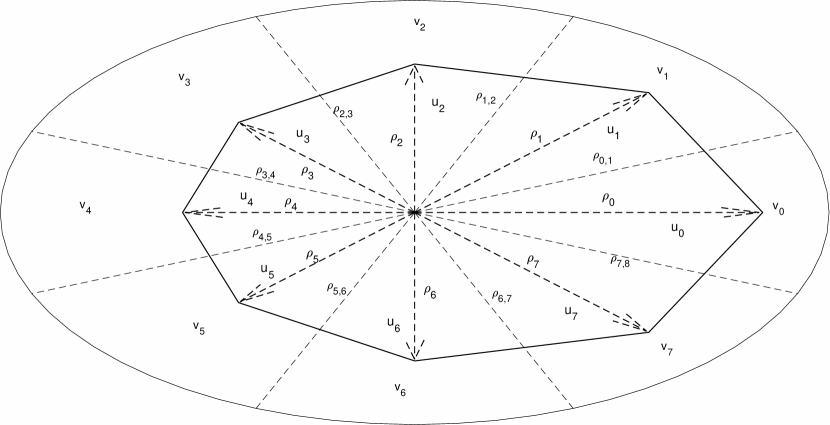

A major shortcoming in existing AC algorithms is that they define similar energy terms for all contour points, despite the fact that intensity and shape vary across the region of interest. To overcome this problem, the proposed algorithm weights the energy terms locally. For example, if part of the IJV contour is obscured by shadow then the algorithm assigns smaller weights to the external energy of the points in the shadowed region such that increased emphasis is on the internal energy terms. Similarly, if a part of the contour has a sharp curvature, the algorithm gives a smaller weight to the curvature energy term for points in areas with sharp edges. These small, non-zero weights enable the contour points to have larger curvatures while still contributing to the total energy. Furthermore, regional variations in intensity are incorporated by subdividing the region of interest (ROI) into multiple sectors with each sector containing one contour point and values of and calculated locally as shown in Fig. (4).

where is the maximum radius of the search area. In this paper, is set to be 50 percent larger than the maximum contour radius, , estimated in previous frame.